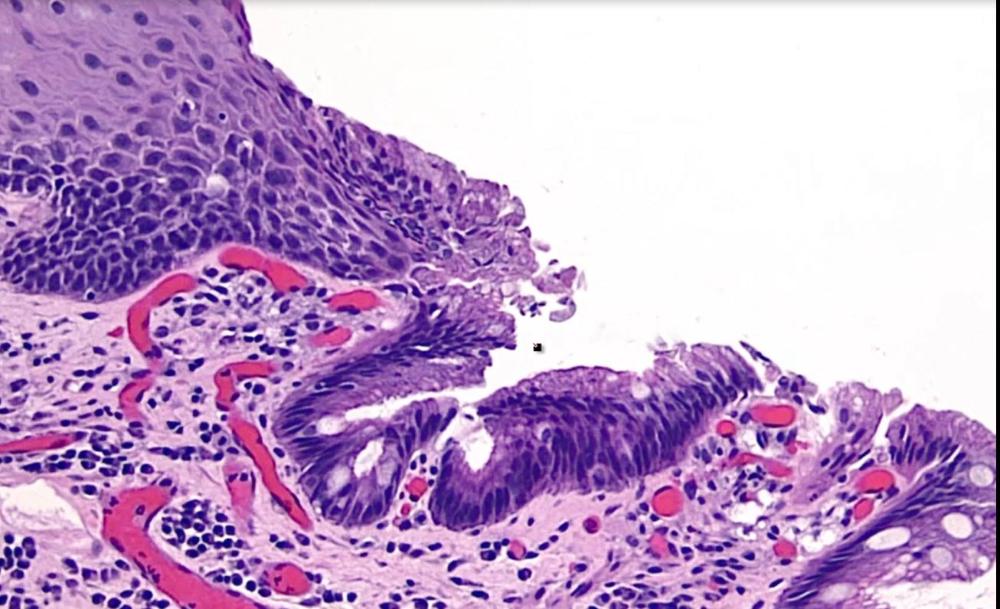

card image

what is this?

signet ring cell